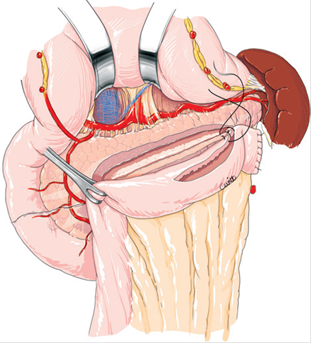

Sección del intestino delgado a nivel de la segunda asa yeyunal, con cierre del extremo distal de la misma y ascenso del asa por vía transmesocólica. Apertura del asa por su borde antimesentérico y confección de la anastomosis yeyuno-pancreática (Wirsung) latero-lateral con puntos separados con poliglactina en 2 planos (Figura 3).

Fig. 3: Derivación Wirsung-yeyunal. Apertura del conducto de Wirsung por su cara anterior y apertura del asa yeyunal por su borde antimesentérico. Anastomosis Wirsung-yeyunal. Tomado de (6).

En 1958, Puestow y Gillesby 3 describe la técnica que lleva su nombre que consiste en una pancreatectomía distal, esplenectomía y derivación del conducto pancreático mediante inserción del páncreas en una yeyunostomía en Y de Roux. Posteriormente, en 1960, Partington y Rochelle 4 describen la sutura del conducto pancreático a un asa yeyunal, logrando de esa manera la derivación del conducto pancreático y evitando la resección pancreática y esplénica. Dicho procedimiento se conoce actualmente como derivación Wirsung-yeyunal, pancreático-yeyunostomía latero-lateral, procedimiento de Puestow modificado o de Partington - Rochelle (Figura 3).